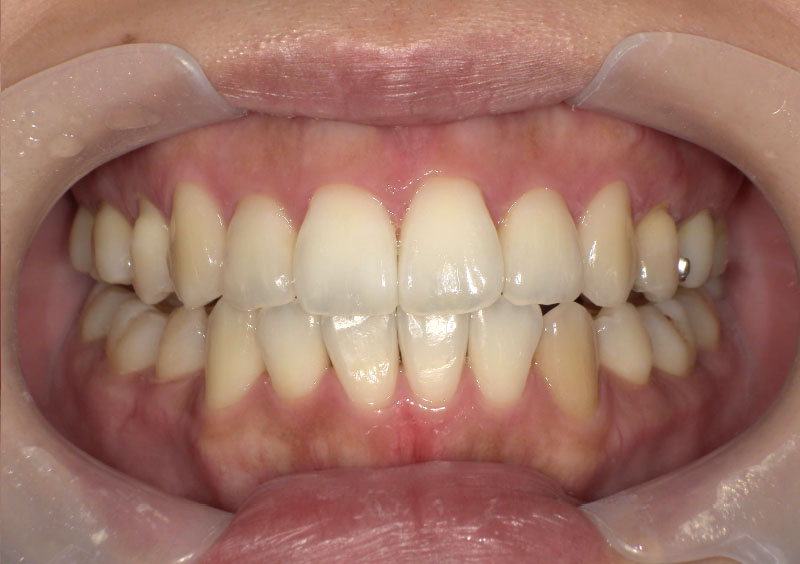

症例04

治療前

治療中

治療後

主訴 | 出っ歯と前歯がガタガタ。 |

治療期間 | 1年6ヶ月 |

治療費 | ¥194,400(税込) |

治療内容 | 上下顎に床矯正装置を使用、 その後下のみ1装置追加。 |

治療のリスク | すでに犬歯が生えている状態での 床矯正治療開始となり、 治療の進み方によってはブラケット治療が 必要になる可能性があったが、 順調に進み、床矯正のみで対応できた。 |